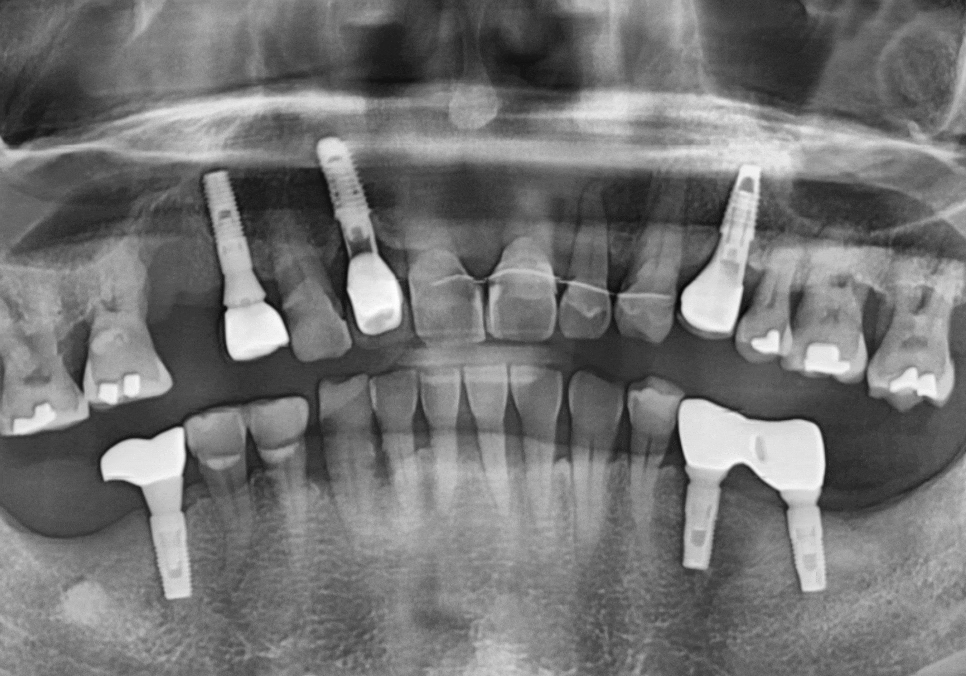

하지만, 방사선 사진과 입안을 살펴보니,

오른쪽 작은 어금니(#15) : 발치로 인해 치아 상실된 상태, 뼈가 다량 녹은 상태

앞니 3개 (#11,21,22) : 복합 치주염으로 뼈가 녹아 잇몸 상태가 좋지 않고 흔들림이 심함

250106 기존 뼈보다 녹은 뼈 상태